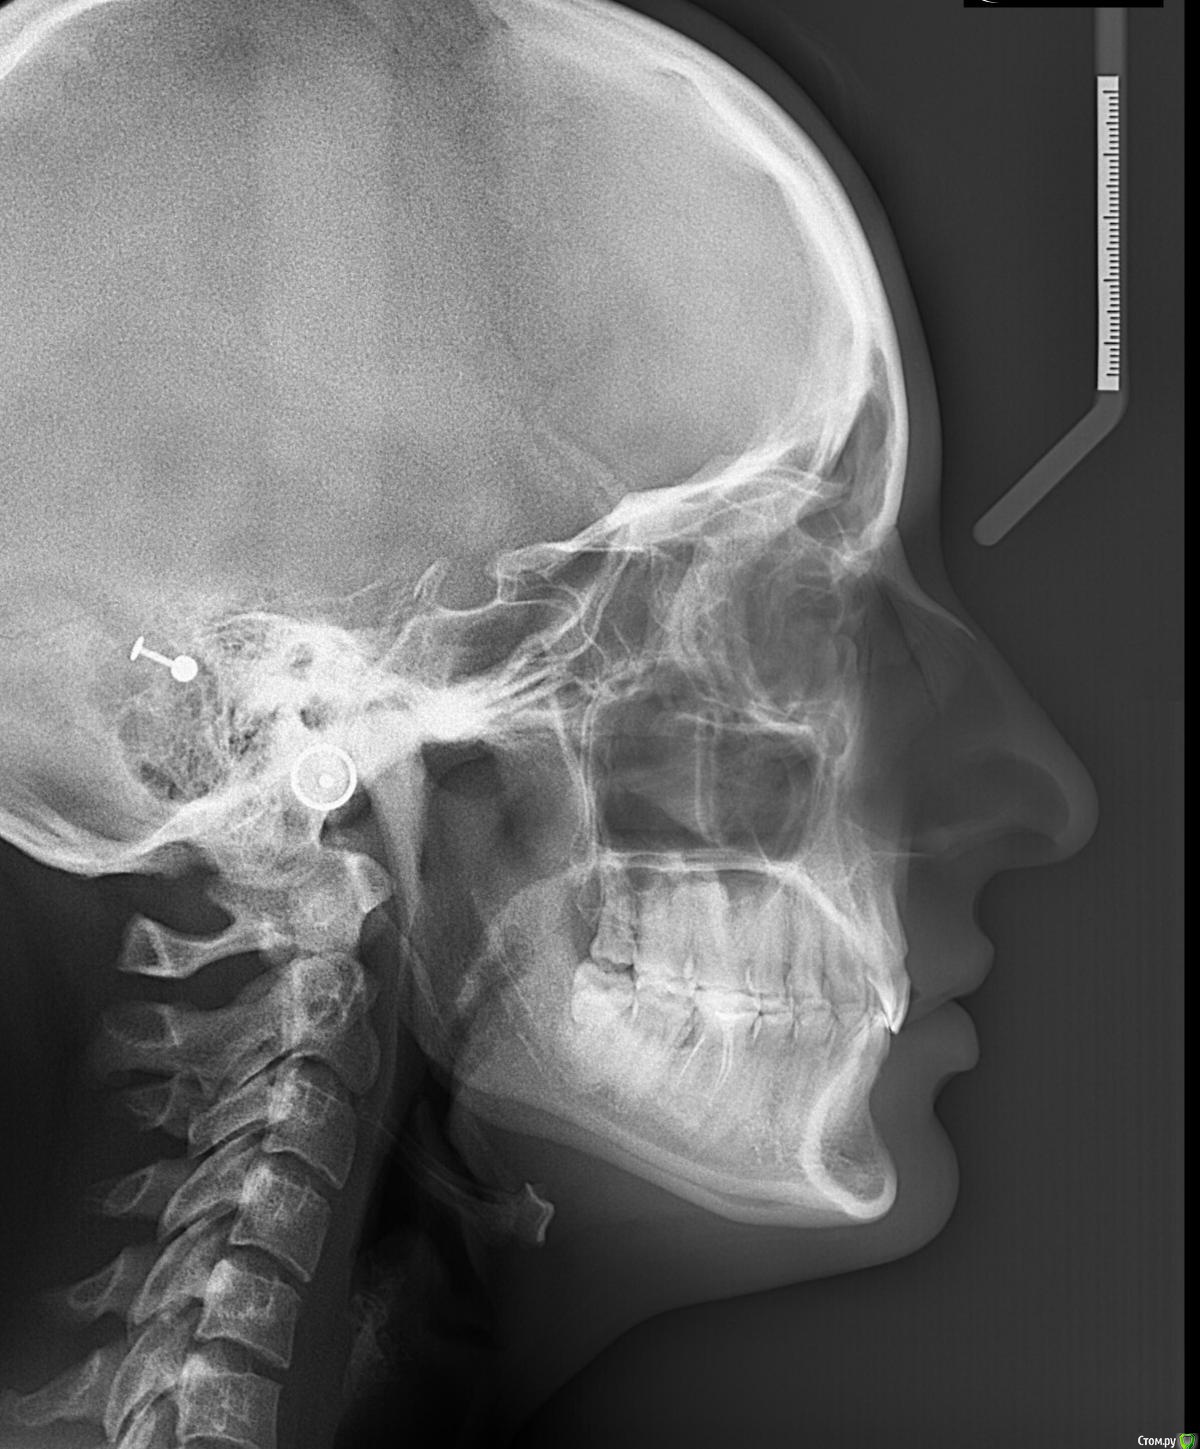

Larnary Опубликовано 28 июля, 2015 Автор Поделиться Опубликовано 28 июля, 2015 (изменено) Видно окклюзионнык интерференции в области 37 и 47.На днях удален 38 и дальше будут удалены остальные восьмерки. На ТРГ мне видится небольшая ретрузия верхних резцов,дистальный прикус. Так же левпя окклюзионная кривая более выраженная,чем правая Изменено 28 июля, 2015 пользователем Larnary 1 Ссылка на комментарий

Skip Опубликовано 29 июля, 2015 Поделиться Опубликовано 29 июля, 2015 На ТРГ мне видится небольшая ретрузия верхних резцов,дистальный прикус. Так же левпя окклюзионная кривая более выраженная,чем правая Доброе утро! Если отталкиваться от анализа ТРГ, то там нет выраженного дистального прикуса, хотя какие-то 0,2 мм. присутствуют, но это ерунда. Скелетное соотношение челюстей Класс I, но есть другая проблема, которая на скриншоте ниже обведена красным: http://i10.pixs.ru/storage/5/2/2/65456789jp_9935083_18202522.jpg Skeletal Deep bite или Скелетный глубокий прикус. Заметьте, не Зубной глубокий прикус, а именно Скелетный и это будет работать в Вашу пользу при планировании лечения. Если встречается комбинация глубокого Зубного и Скелетного, то эти случаи сложнее открыть. http://i11.pixs.ru/storage/5/3/1/0987645678_6395482_18202531.jpg В отношении верхних резцов, то всё правильно Вы отметили, они действительно в ретрузии (-4 мм.) и угол их инклинации уменьшен, как собственно и угол инклинации нижних резцов, а другими словами, мы имеем соотношение резцов 2-го подкласса. Это обстоятельство служит достаточно высоким риском развития внутрикапсулярных проблем ВНЧС. В вашем случае, интуиция мне как-то подсказывает, что там вероятно существует гипермобильность, но могу и ошибаться. Резцы 2-го подкласса могут объяснить и стриаемость этих зубов, учитывая, как Вы наверное знаете, дисгармонию между углом суставного пути и угла инклинации резцов Но вот ещё одно обстоятельство, на которое хотелось бы обратить внимание и которое нужно отметить в Вашем проблемном списке. Опять же, исходя из анализа ТРГ. Из этого анализа следует, что верхняя челюсть длинная и расположена в ретропозиции. Вы это никак уже не измените, но как при этом будет вести себя нижняя челюсть? Из собственной практики, я заметил, что нижняя челюсть, при этих обстоятельствах, частенько позиционируется кпереди в центральной окклюзии, обеспечивая, тем самым, нормализацию такой жизненно важной функции, как дыхание. И если Вы проведёте, к примеру, нейромышечную регистрацию физиологического положения нижней челюсти, а иными словами регистрацию прикуса, то вполне сможете обнаружить, что нижняя челюсть окажется в ретроположении. И получаем, в итоге, такой недоделанный природой Класс II, так ведь..? Это как раз то, когда повышая прикус, мы, впоследствии, сталкиваемся с проблемой т.н. двойного прикуса. Может нижняя челюсть и сметала всё мешающее ей на своём пути, когда постоянно стремилась находиться кпереди..? Кстати, при 2-ом классе нижняя челюсть практически всегда любит находится чуть кпереди, но это так, для кругозора... Есть ещё одно обстоятельство, которое может наносить сокрушительный удар по твёрдым структурам зубов. Оговорюсь сразу, что я не сторонник разных там теорий, так или иначе связанных с психикой, стрессом и так далее. В связи с этим у меня к Вам вопрос. Вы проводили монтаж моделей в артикуляторе с лицевой дугой или по средним значениям? Если с лицевой дугой, то хотелось бы взглянуть, как там модель верхней челюсти расположена в пространстве артикулятора. Нет ли там бокового смещения модели от центра верхней рамы..? То, что с левой стороны окклюзионная кривая глубже, то это носит адаптационной характер, связанный с левым суставом, поэтому нужно провести мониторинг ВНЧС, на предмет внутрикапсулярных расстройств этого сочленения (объём вертикальных и горизонтальных движений ROM). На ТРГ, кстати, можно заметить, как раздваивается нижний край тела нижней челюсти и это неспроста. 3 Ссылка на комментарий

Skip Опубликовано 29 июля, 2015 Поделиться Опубликовано 29 июля, 2015 А в какой программе Вы делали расчет ТРГ? AudaxCeph. Сам анализ называется Sassouni Plus. 1 Ссылка на комментарий